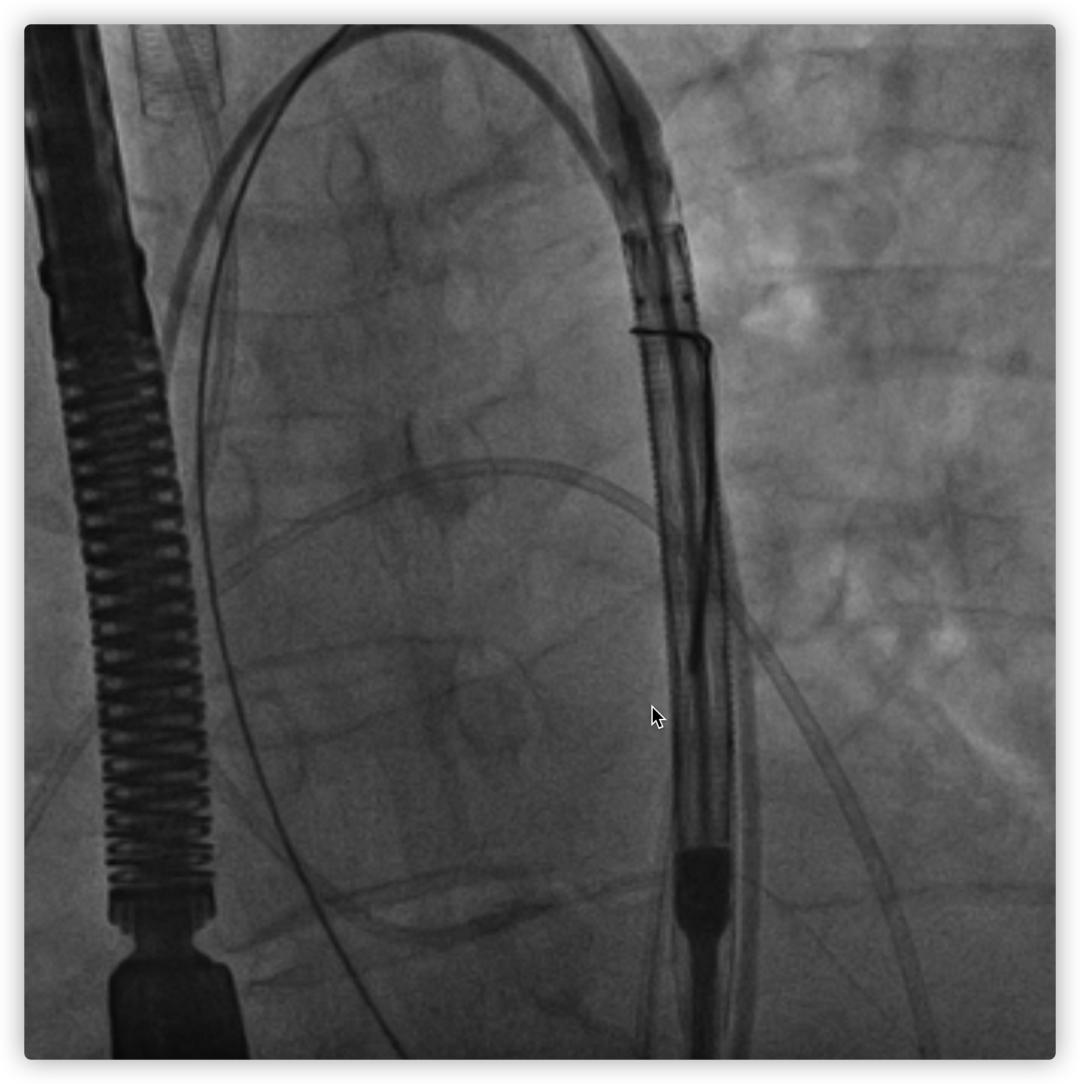

26VenusAplus+snare

LM烟囱支架植入4.0*30mm